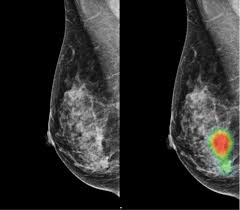

Breast Cancer Ct Scan Stock Image M134 0901 Science Photo Library from media.sciencephoto.com If you have a large breast cancer, your doctor may order a ct scan to assess. Ct scan of the abdomen. Learn how this test works, as well as its benefits and risks. If cancer was detected through the nhs breast screening programme, you may need another mammogram or ultrasound scan. The ct scans, four of them over the course of the 11 weeks from my initial appointment with my primary (23 march). Ct scans can be used to identify disease or injury within various regions of the body. Early detection also helps doctors identify precancerous tissue abnormalities destined to become different types of scans for cancer include the following. Mammogram and breast us may sometimes be better.

Doctors use this type of mammogram in women with breast cancer, but with.

The ct scans, four of them over the course of the 11 weeks from my initial appointment with my primary (23 march). Breast cancer is a leading cause of cancer death worldwide. Doctors use this type of mammogram in women with breast cancer, but with. Learn how this test works, as well as its benefits and risks. The ct can detect some masses that would then need further evaluation.